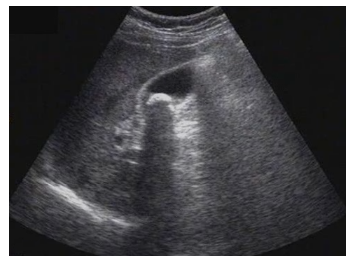

試題3:患者女性,50歲,間斷上腹隱痛半年,診斷為(2分)

A.肝癌

B.肝硬化

C.膽囊結(jié)石

D.腎結(jié)石

E.急性膽囊炎

【答案】C